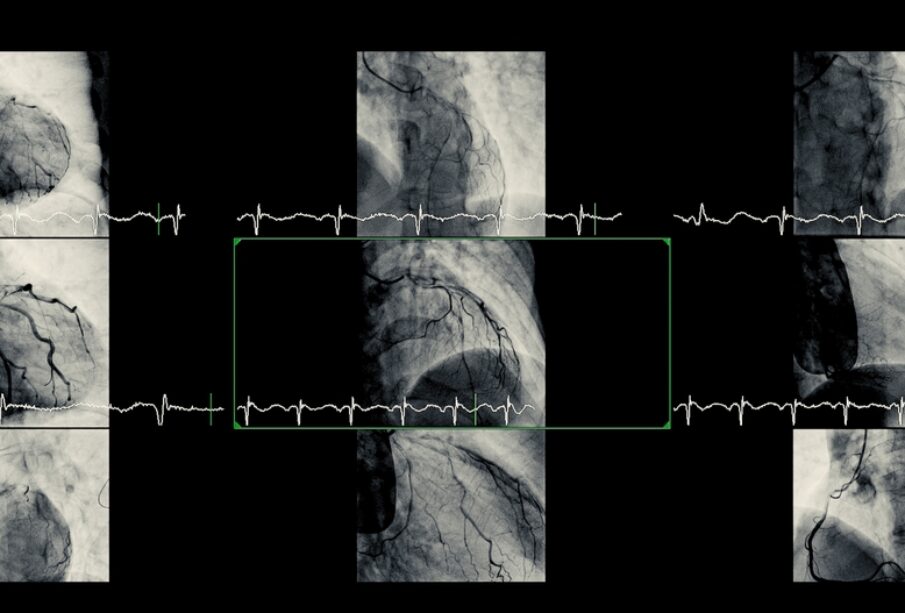

Angiografija yra invazinis tyrimas: per kraujagysles įvedamas kateteris, kuriuo įleidžiamos kontrastinės medžiagos, ir tuo pačiu metu atliekami rentgeno ar ultragarsiniai vaizdai. Šis tyrimas leidžia tiesiogiai matyti arterijų padėtį, įvertinti užsikimšimo laipsnį ir kraujotaką per širdies kraujagysles.